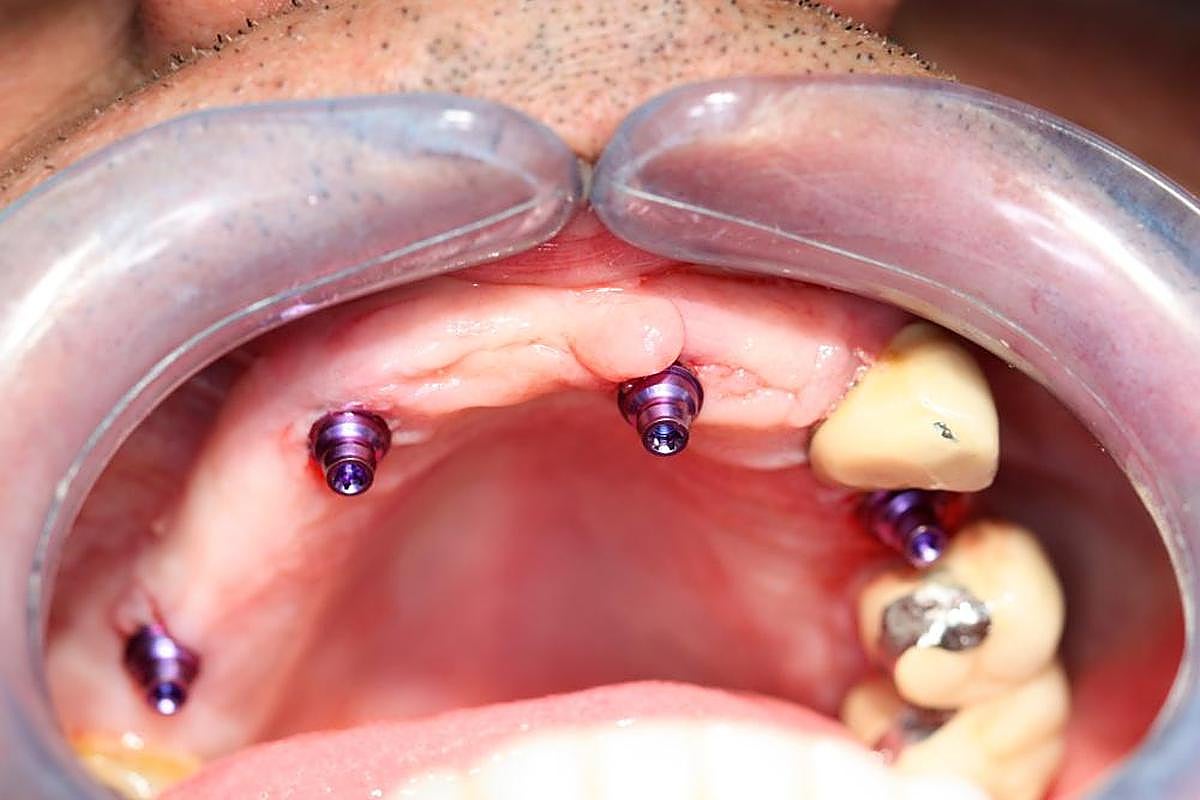

PASO 6. El paciente, con los dispositivos del implante colocados.

El siguiente paso es elaborar una férula quirúrgica que hace las funciones de guía para colocar los implantes tal y como se ha planificado previamente. En el momento de la intervención, la prótesis se sitúa en la boca del paciente para atornillar con precisión milimétrica todos los implantes. “De esta forma nos aseguramos un menor riesgo para el paciente, un posoperatorio mejor y un menor tiempo de intervención para que se vaya a casa con unos dientes fijos en el momento”, asegura el doctor Alfonso Sanz Albornos.